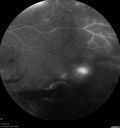

50 year old man: The patient noticed a few days ago, when putting on Contact Lenses for work which were slightly different from his usual strength. He therefore had some trouble at work with the new contact lenses. Then he had some haze in his vision. In the morning he went to see his mother in Venice and there was a new big black line in the left eye when he was getting up from lying down (this was yesterday). Then he noticed a lot of floaters in his vision that looked like blood. This has been fluctuating. You saw him this morning and asked him to come here. VA OD: Dcc20/20-2 NscJ1+ The patient has type I diabetes diagnosed at age 24 and he is now 50 years old VA OS: Dcc20/25+2 NscJ1+ IOP: TP: OD:17 OS:19

PDR and Vitreous Hemorrhage - High Risk Left Eye - Low Risk Right Eye412 views50 year old man with type I diabetes mellitus for 26 years. New Vitreous Hemorrhage in the left eye. Both eyes have NVE. Both also have foveal hypoplasia00000